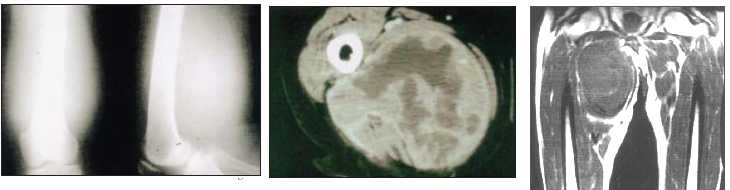

Typically a sarcoma was a large tumor that would grow out of the deep tissues in the leg (see historical picture from 1816 here and from 1920 here).

They are usually well seen on an MRI (go here ,here and here).

Patient with a large sarcoma in the right anterior thigh: CT here, MRI here and here, PET after neoadjuvant chemotherapy here and here